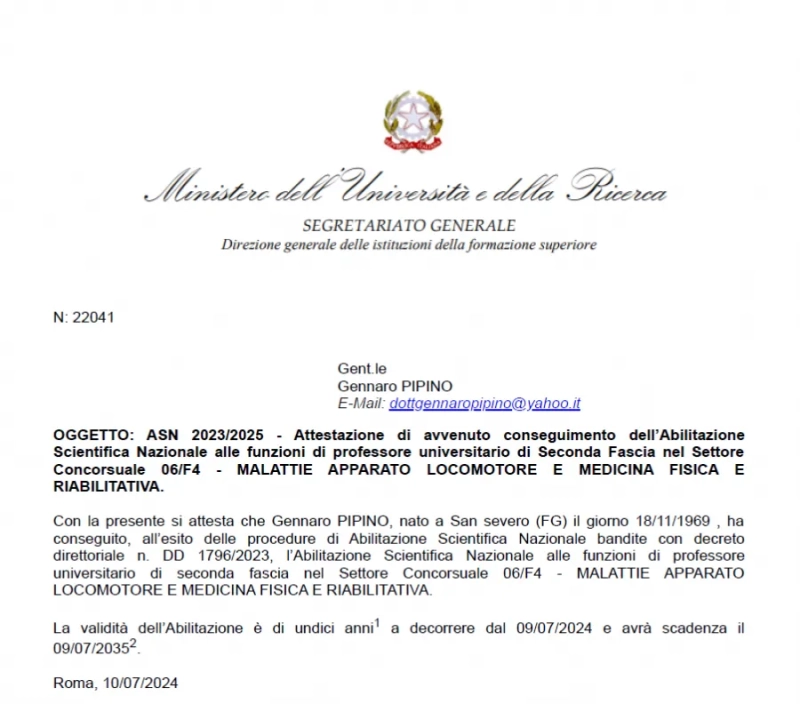

Prof. Pipino Gennaro, outsider a livello internazionale nella Chirurgia protesica di ginocchio mediante sistemi digitali ed intelligenza artificiale nel rispetto degli assi meccanici ed il ripristino totale della anatomia e cinematica del ginocchio protesizzato.

- Responsabile dell’Unità Operativa Ortopedia III presso Casa di Cura Villa Erbosa di Bologna;

- Professore a contratto della Scuola di Specializzazione in Ortopedia e Traumatologia presso l’Università Vita - Salute San Raffaele di Milano;

- Progettista di sistemi innovativi protesici mini-invasivi per ortopedia;

- Responsabile mondiale del primo studio per trapianti di cartilagine con azienda statunitense OLIGOMEDIC per il trapianto Joint REP;

- Progettista e titolare del brevetto dell’allineatore Trans Epicondilare per chirurgia protesica di ginocchio.